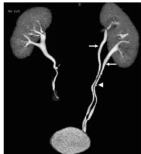

看清血管的「交通状况」

注射造影剂后,血管变成「发光公路」,能精准发现: